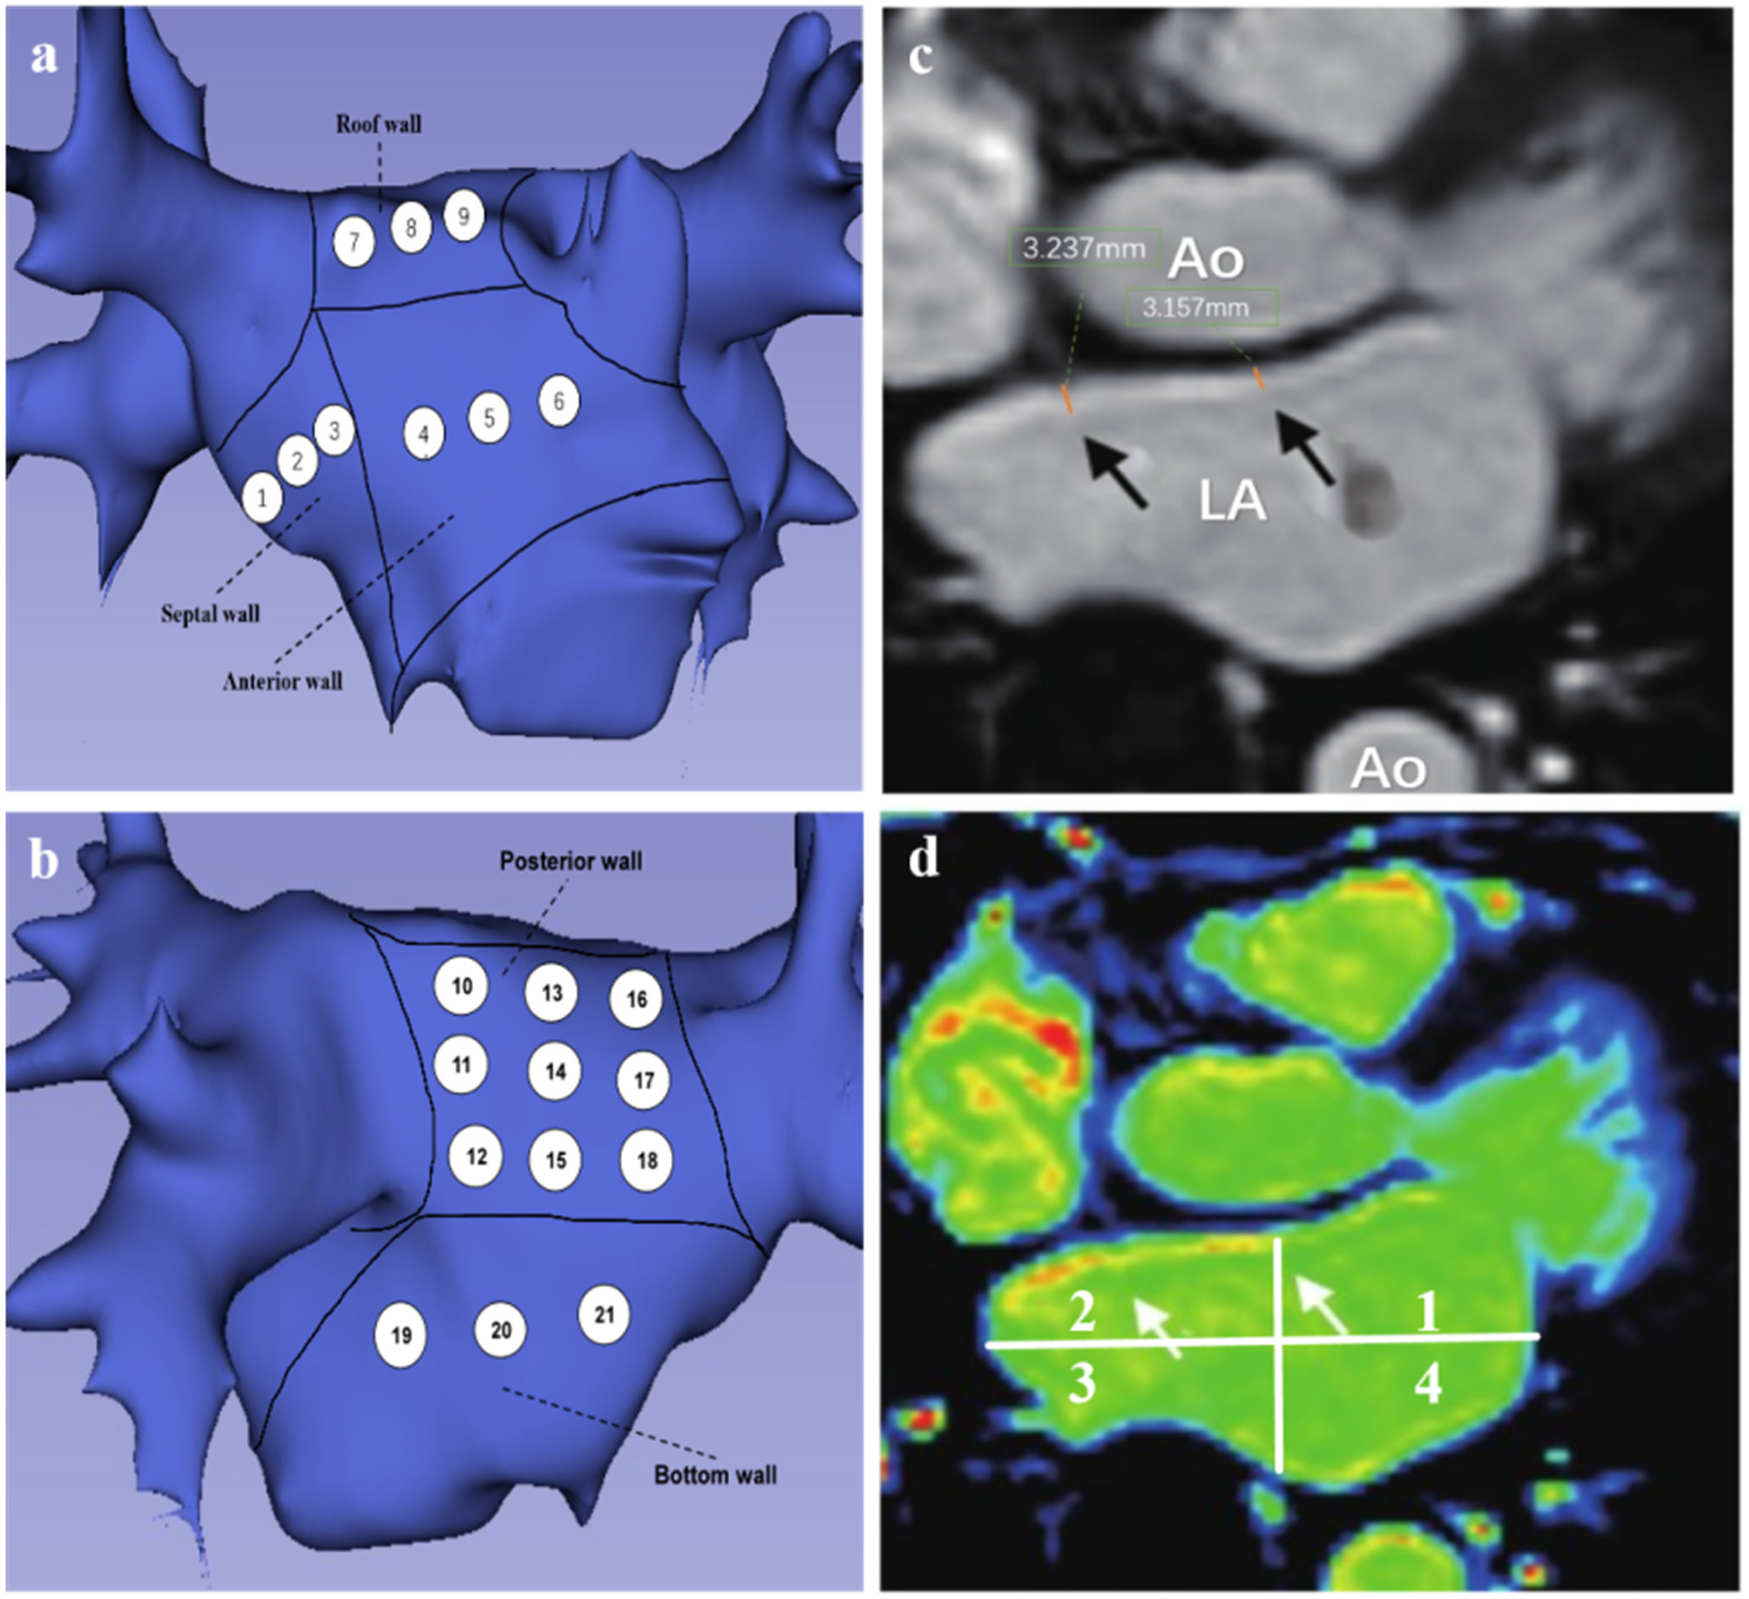

Figure 2

(a,b) Patterns of left atrial segment measurements. (a) Left atrial anteroposterior position, 1–3 represents the region of interstitial wall thickness measurement, 4–6 represents the region of AWT measurement, and 7–9 represents the region of RWT measurement. (b) Posterior-anterior position, 10–18 represents the PWT measurement region, 19–21 represents the BWT measurement region. (c,d) Representative LGE-MRI images of the left atrium. (c) Black arrows are examples of LAWT measurements. (d) magnetic resonance image of delayed enhancement zones (axial position), white arrows point to red and yellow zones representing fibrotic zones.